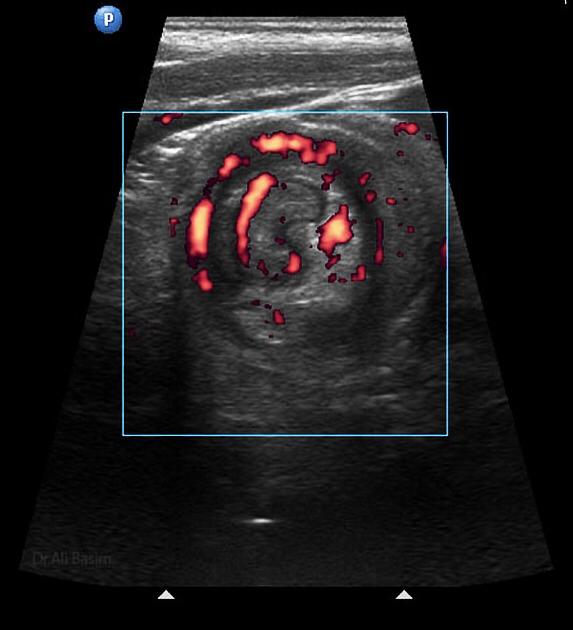

La invaginación intestinal es la causa más común de obstrucción intestinal en niños de 3 meses a 3 años. Se caracteriza porque un segmento de intestino penetra en otro segmento intestinal. Puede presentarse en colon, intestino delgado o entre intestino delgado y el colon. El resultado es la obstrucción intestinal.